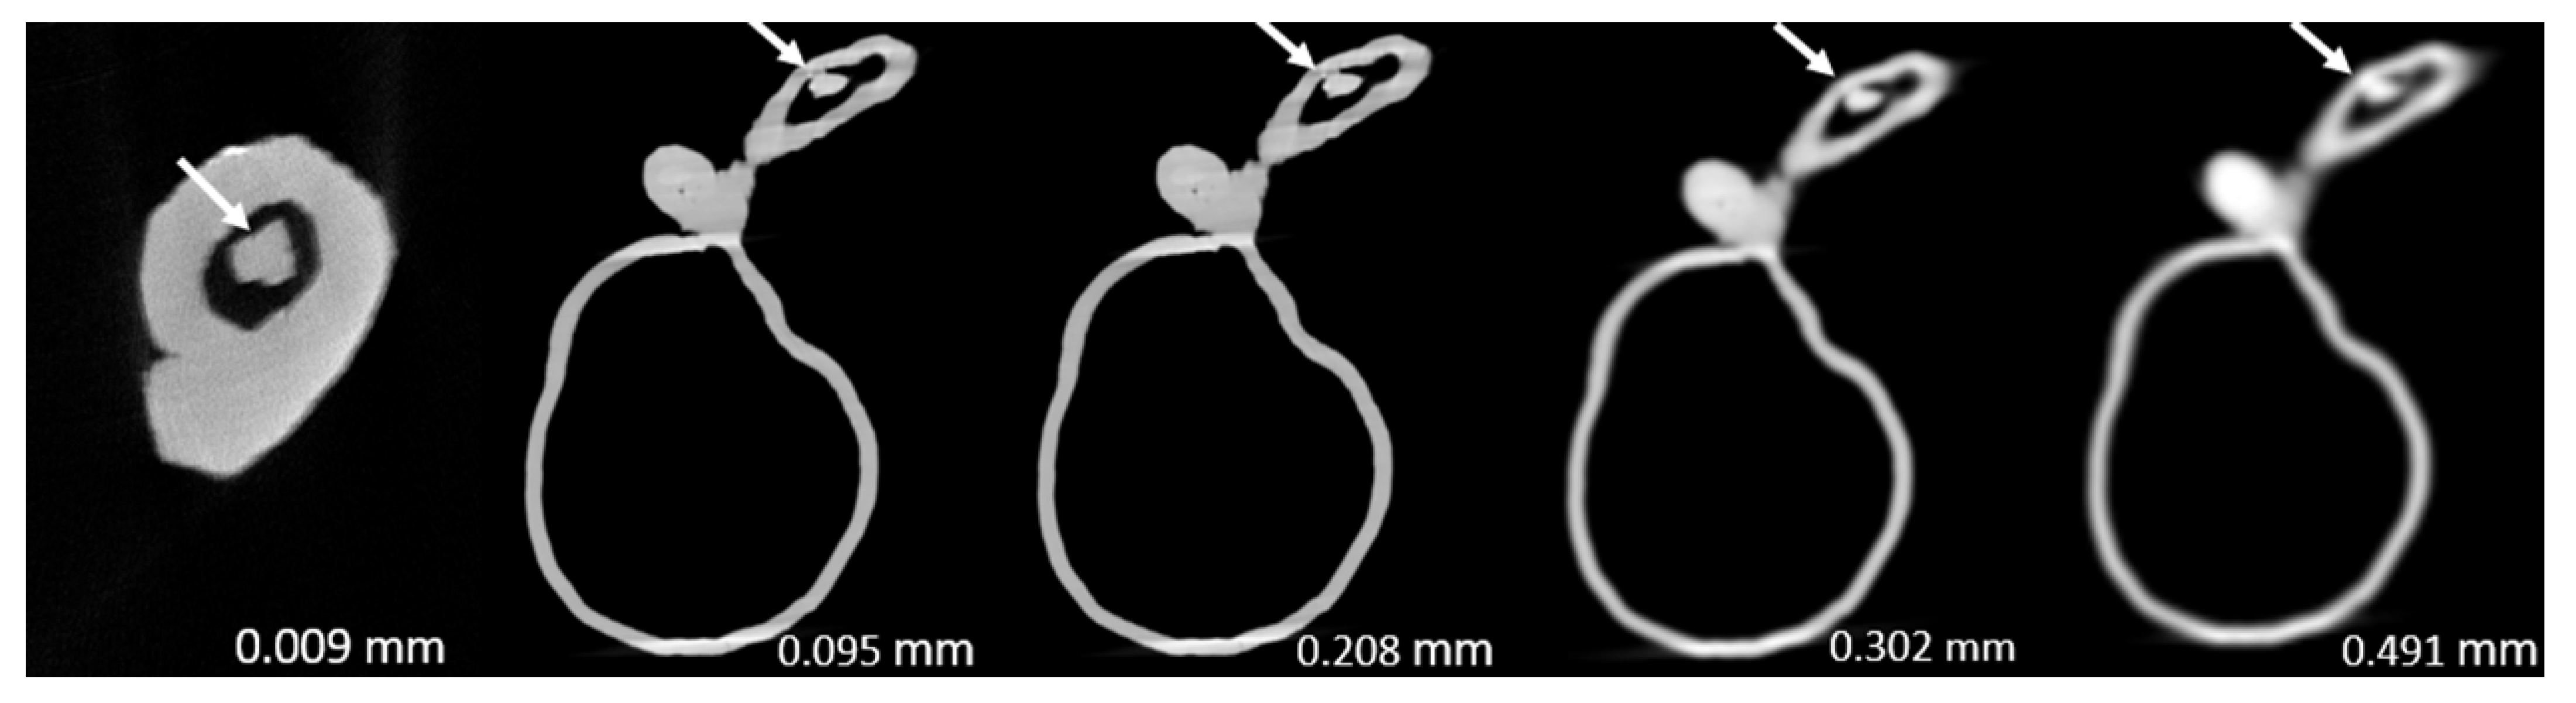

- Model 1: >90% and <50% stenosis in left main stem (LM) and left anterior descending (LAD) coronary artery, respectively.

| 1 | 86.2 ± 0.033 | 99.1 ± 0.004 | 98.8 ± 0.003 | 99.1 ± 0.004 | 100 ± 0.000 | <0.005 |

| 2 | 80.0 ± 0.044 | 97.2 ± 0.025 | 97.8 ± 0.022 | 96.4 ± 0.012 | 96.4 ± 0.010 | <0.0005 |

| 3 | 94.4 ± 0.000 | 99.2 ± 0.005 | 97.2 ± 0.009 | 97.8 ± 0.005 | 100 ± 0.000 | <0.0005 |